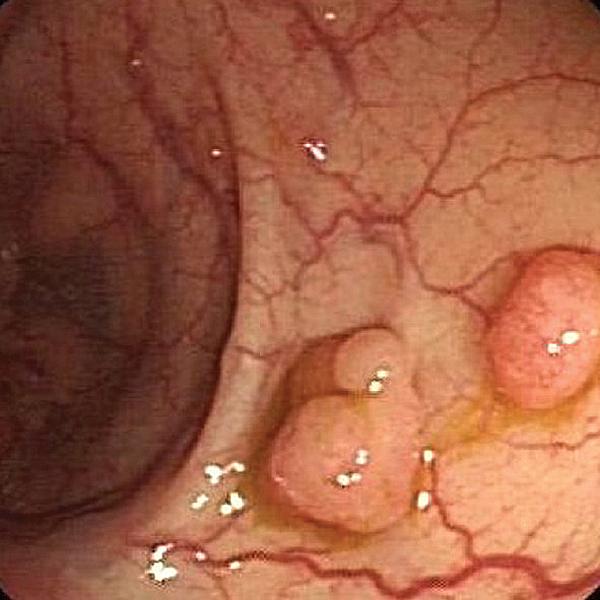

最近几年收治了一些特殊的病例,因为口唇发黑就诊,诊断考虑有胃肠道息肉,其实如果非胃肠专科的医生,可能都很少见得到这种病例。

它的学名叫做黑斑息肉综合征(波伊茨一耶格综合征,Peutz 一Jeghers syndrome )又称色素沉着息肉综合征。

它是一种常染色体显性遗传病,约50 %患者有明显家族史。主要表现为面部、口唇周围和颊钻膜的色素沉着,以及胃肠道多发息肉,病理上为错构瘤。

这种疾病通常除了口唇有黑斑以外,没有明显的症状,如果胃肠道息肉较大时会出现腹痛、便血症状,甚至可能会导致肠梗阻,肠套叠,贫血等症状,严重时危机生命。而且该疾病具有一定的癌变几率。

它的治疗一般可以通过肠镜下息肉切除,或者是手术切除等方法。 因为这种疾病比较罕见,而且有一定的家族遗传倾向,曾接诊过一家三口:父亲和两个女儿都患有这种疾病,并接受了治疗。